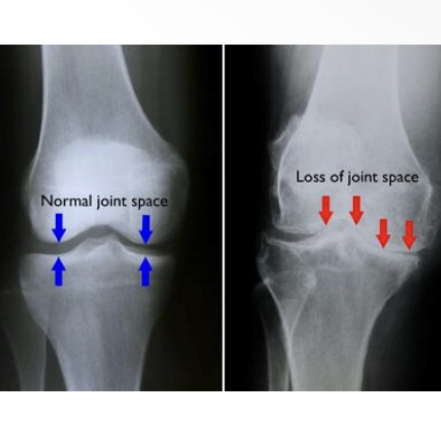

What is osteoarthritis

Degenerative form of arthritis

What are the forms of osteoarthritis

Primary: age related

Secondary: caused by another disease

What happens in osteoarthritis

cartilage degenerates

Joint pain and swelling

Cartilage inflammation will cause bone spurs to form around joints which will hit nerves

Water content in cartilage osteoaritis ____, protein content ___